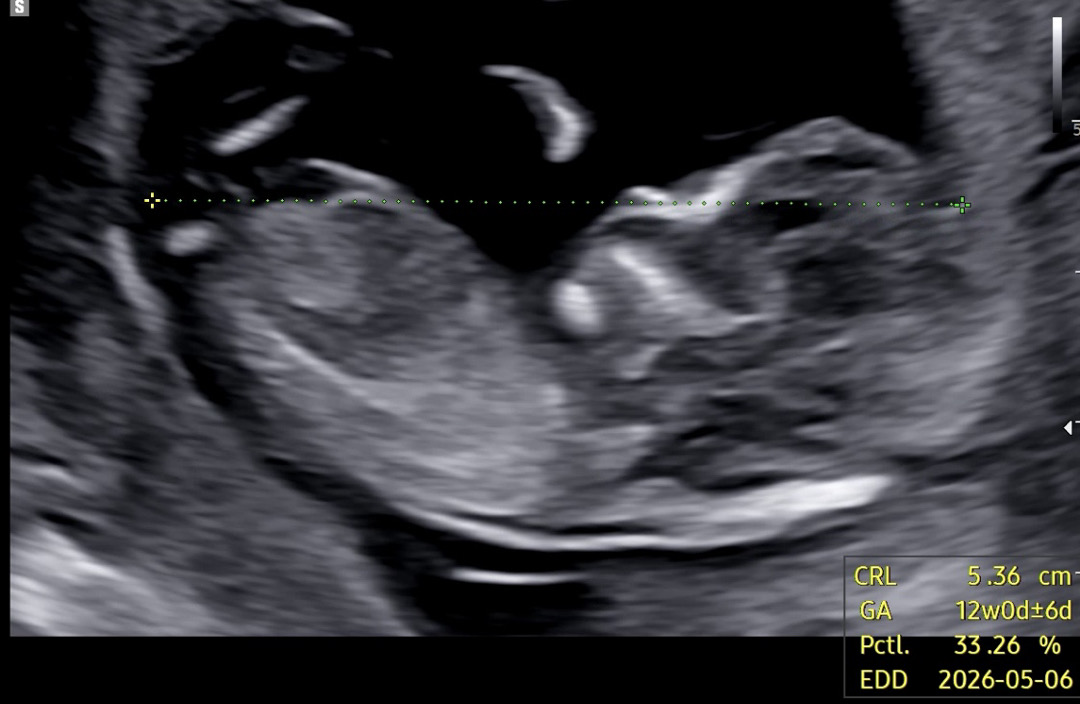

12주2일차 각도법 .ᐟ .ᐟ

오늘 12주차2일째 되는날 기형아 검사, 정밀초음파 까지 보고 왔는데 혹시나 하는 마음에 자세히 봤는데도 아직 알수가 없다고 하더라구요 각도법 잘 보시는 고수님들 확인 부탁드려요:)